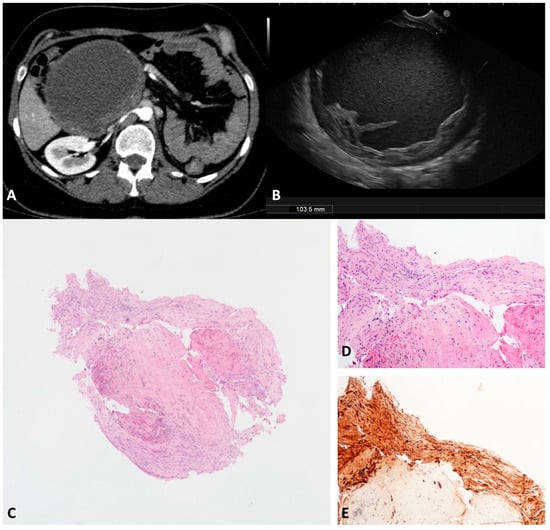

3.9. Schwannoma (SWN)

SWNs originate from peripheral nerve sheath Schwann cells []. The pancreatic/peripancreatic localization of SWNs is extremely rare. Usually, SWNs arise from neighboring sites and secondarily involve the pancreatic gland, but more rarely can originate from pancreatic innervation []. SWNs are usually discovered incidentally as a painless mass in middle-aged patients. Malignant SWNs occur in 59% of patients with sporadic tumors []. SWNs are round or oval capsulated tumors with well-defined margins. Histologically, SWNs comprise two different areas: Antoni A and Antoni B. The first is composed of packed spindle-shaped cells that show immunohistochemistry positivity for protein S-100. The second area is occupied by hypocellular loose stroma and may be the subject of degenerative changes, such as cyst formation, hemorrhage, necrosis, and calcification. Cystic degeneration is related to larger sizes and mimics the whole spectrum of cystic pancreatic lesions. We observed one case of a large (103.5 mm) cystic unilocular SWN incidentally discovered on a transabdominal ultrasound and confirmed on a CT scan of a 40-year-old female (Figure 10A). According to the EUS, a unilocular cyst with a thickened irregular wall and corpuscolated fluid content was documented between the duodenal wall and the pancreatic head (Figure 10B). The TTNB specimens were composed of spindle cells with positive protein S-100 immunohistochemistry staining (Figure 10C–E). The lesion was subsequently surgically resected with confirmation of the diagnosis.

Figure 10.

Schwannoma. Computed tomography appearance of a large cystic lesion located between the second/third portion of the duodenum and the pancreatic head that appeared compressed and dislodged (A). On the endoscopic ultrasound, the lesion appeared as a round unilocular cyst with smooth borders and an irregular thickened wall (B). The whole mounted section of the cyst wall biopsy shows no epithelium lining the cyst (C). A well visible fascicle of spindle cells depicts the peripheral profile of the biopsy (D). Diffuse and intense immunolabelling for S100 in spindle cells (E). Hematoxylin–eosin original magnification ×40 (C), ×100 (D). S100 original magnification ×100 (E).